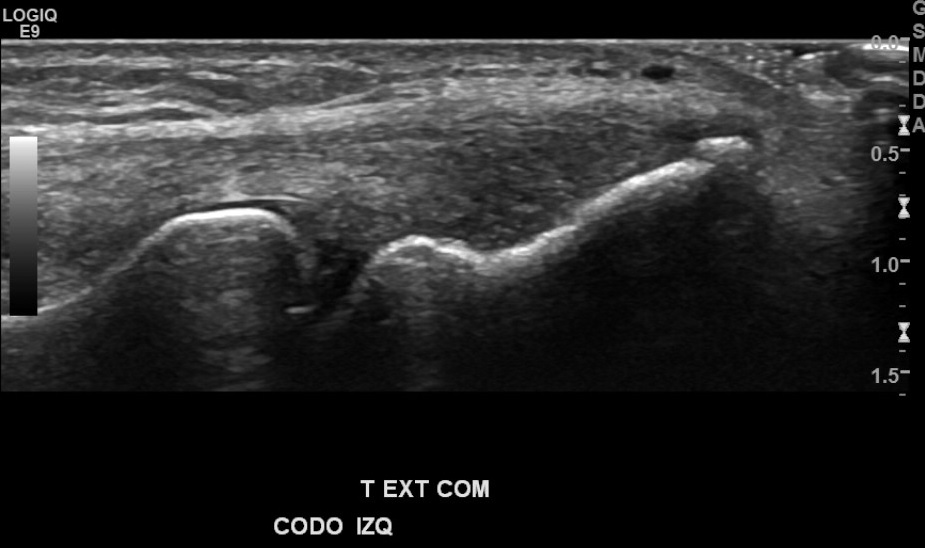

Antecedentes: chequeo por marcado dolor de región epicondilo lateral de codo izquierdo, mayor hace 1 mes aprox., por esfuerzo laboral de EESS, sin trauma.

Hallazgos: marcada heterogeneidad de tendón extensor común izquierdo, con foco de desgarro de espesor y ancho parcial en su espesor, con hiperemia al doppler color.